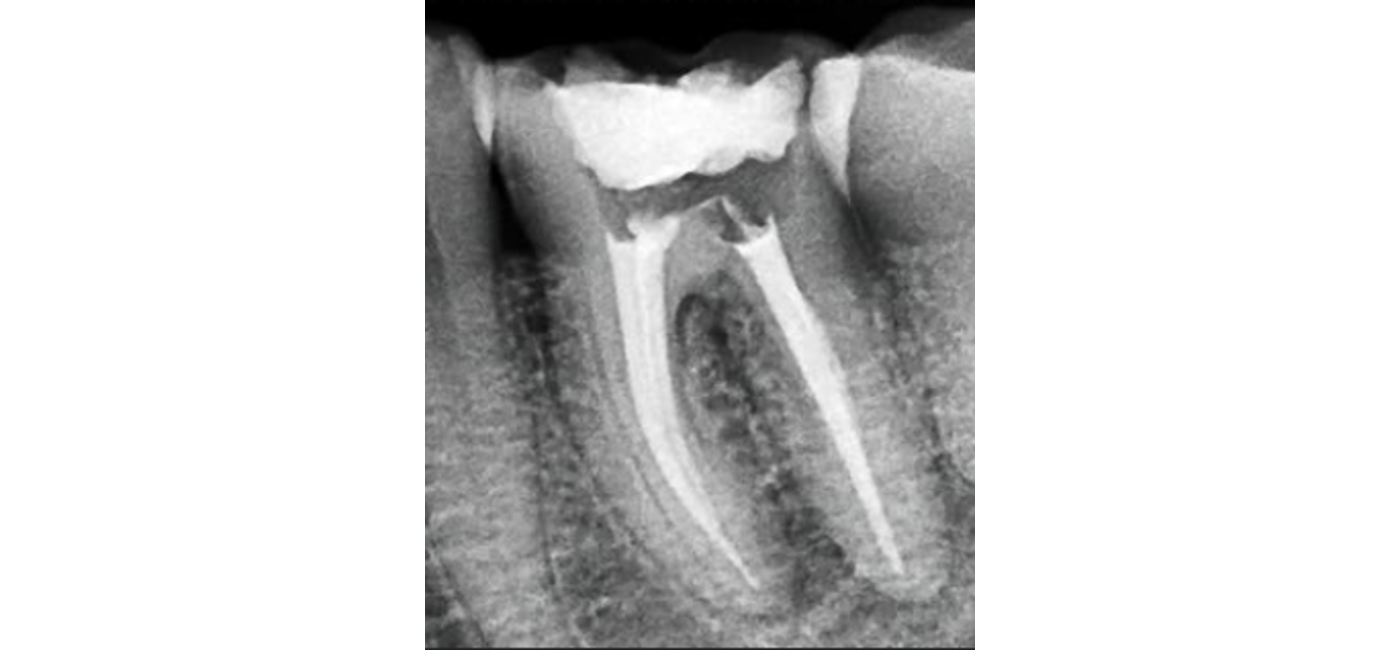

El procedimiento se realiza bajo anestesia local y se lleva a cabo en varias fases. Primero, el odontólogo o endodoncista accede a la cámara pulpar del diente para extraer la pulpa dañada. Luego, se limpian y desinfectan cuidadosamente los conductos radiculares con instrumentos especializados y soluciones antimicrobianas. Posteriormente, estos conductos se rellenan con un material biocompatible, generalmente gutapercha, que sella el interior del diente. Finalmente, se coloca una restauración temporal o definitiva, como una corona, para proteger el diente y devolverle su forma y función.

Gracias a los avances tecnológicos, la endodoncia moderna se realiza con equipos rotatorios, lupas de aumento, radiografías digitales y localizadores electrónicos de ápice, lo que garantiza una mayor precisión, rapidez y confort para el paciente. En la mayoría de los casos, el tratamiento se completa en una o dos sesiones y el alivio del dolor es casi inmediato.